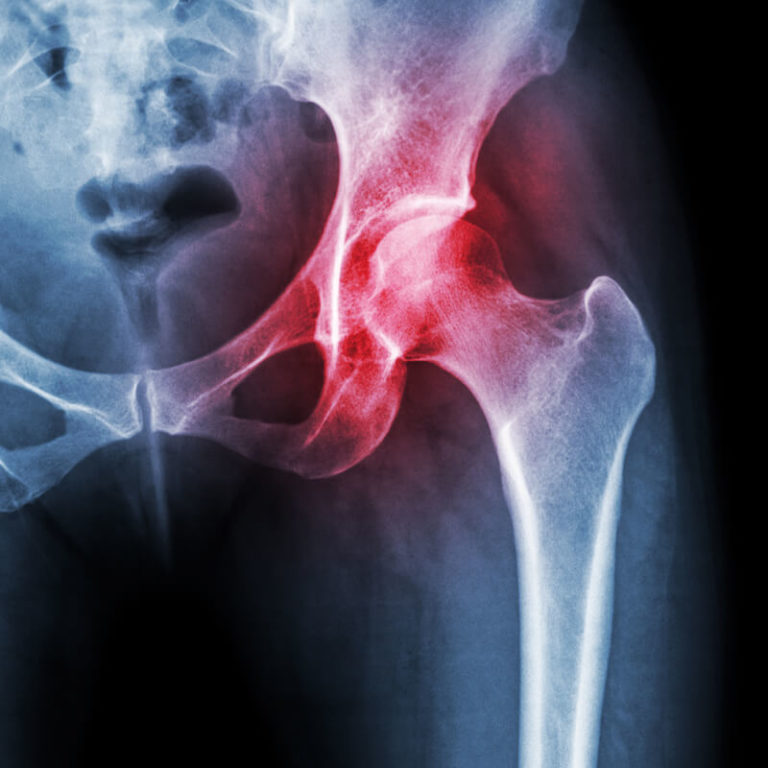

Osteoporosis